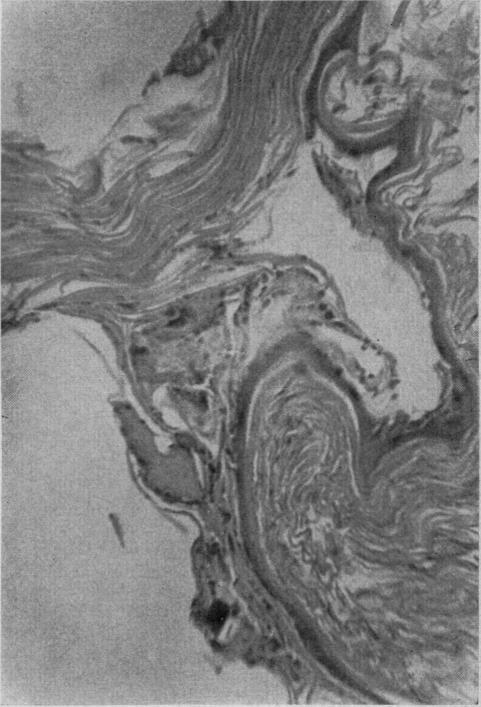

EPIDERMOID CYST OF THE TERMINAL PHALANX OF THE THUMB.

Can Med Assoc J. 1964 Jun 27;90(26):1464-6.